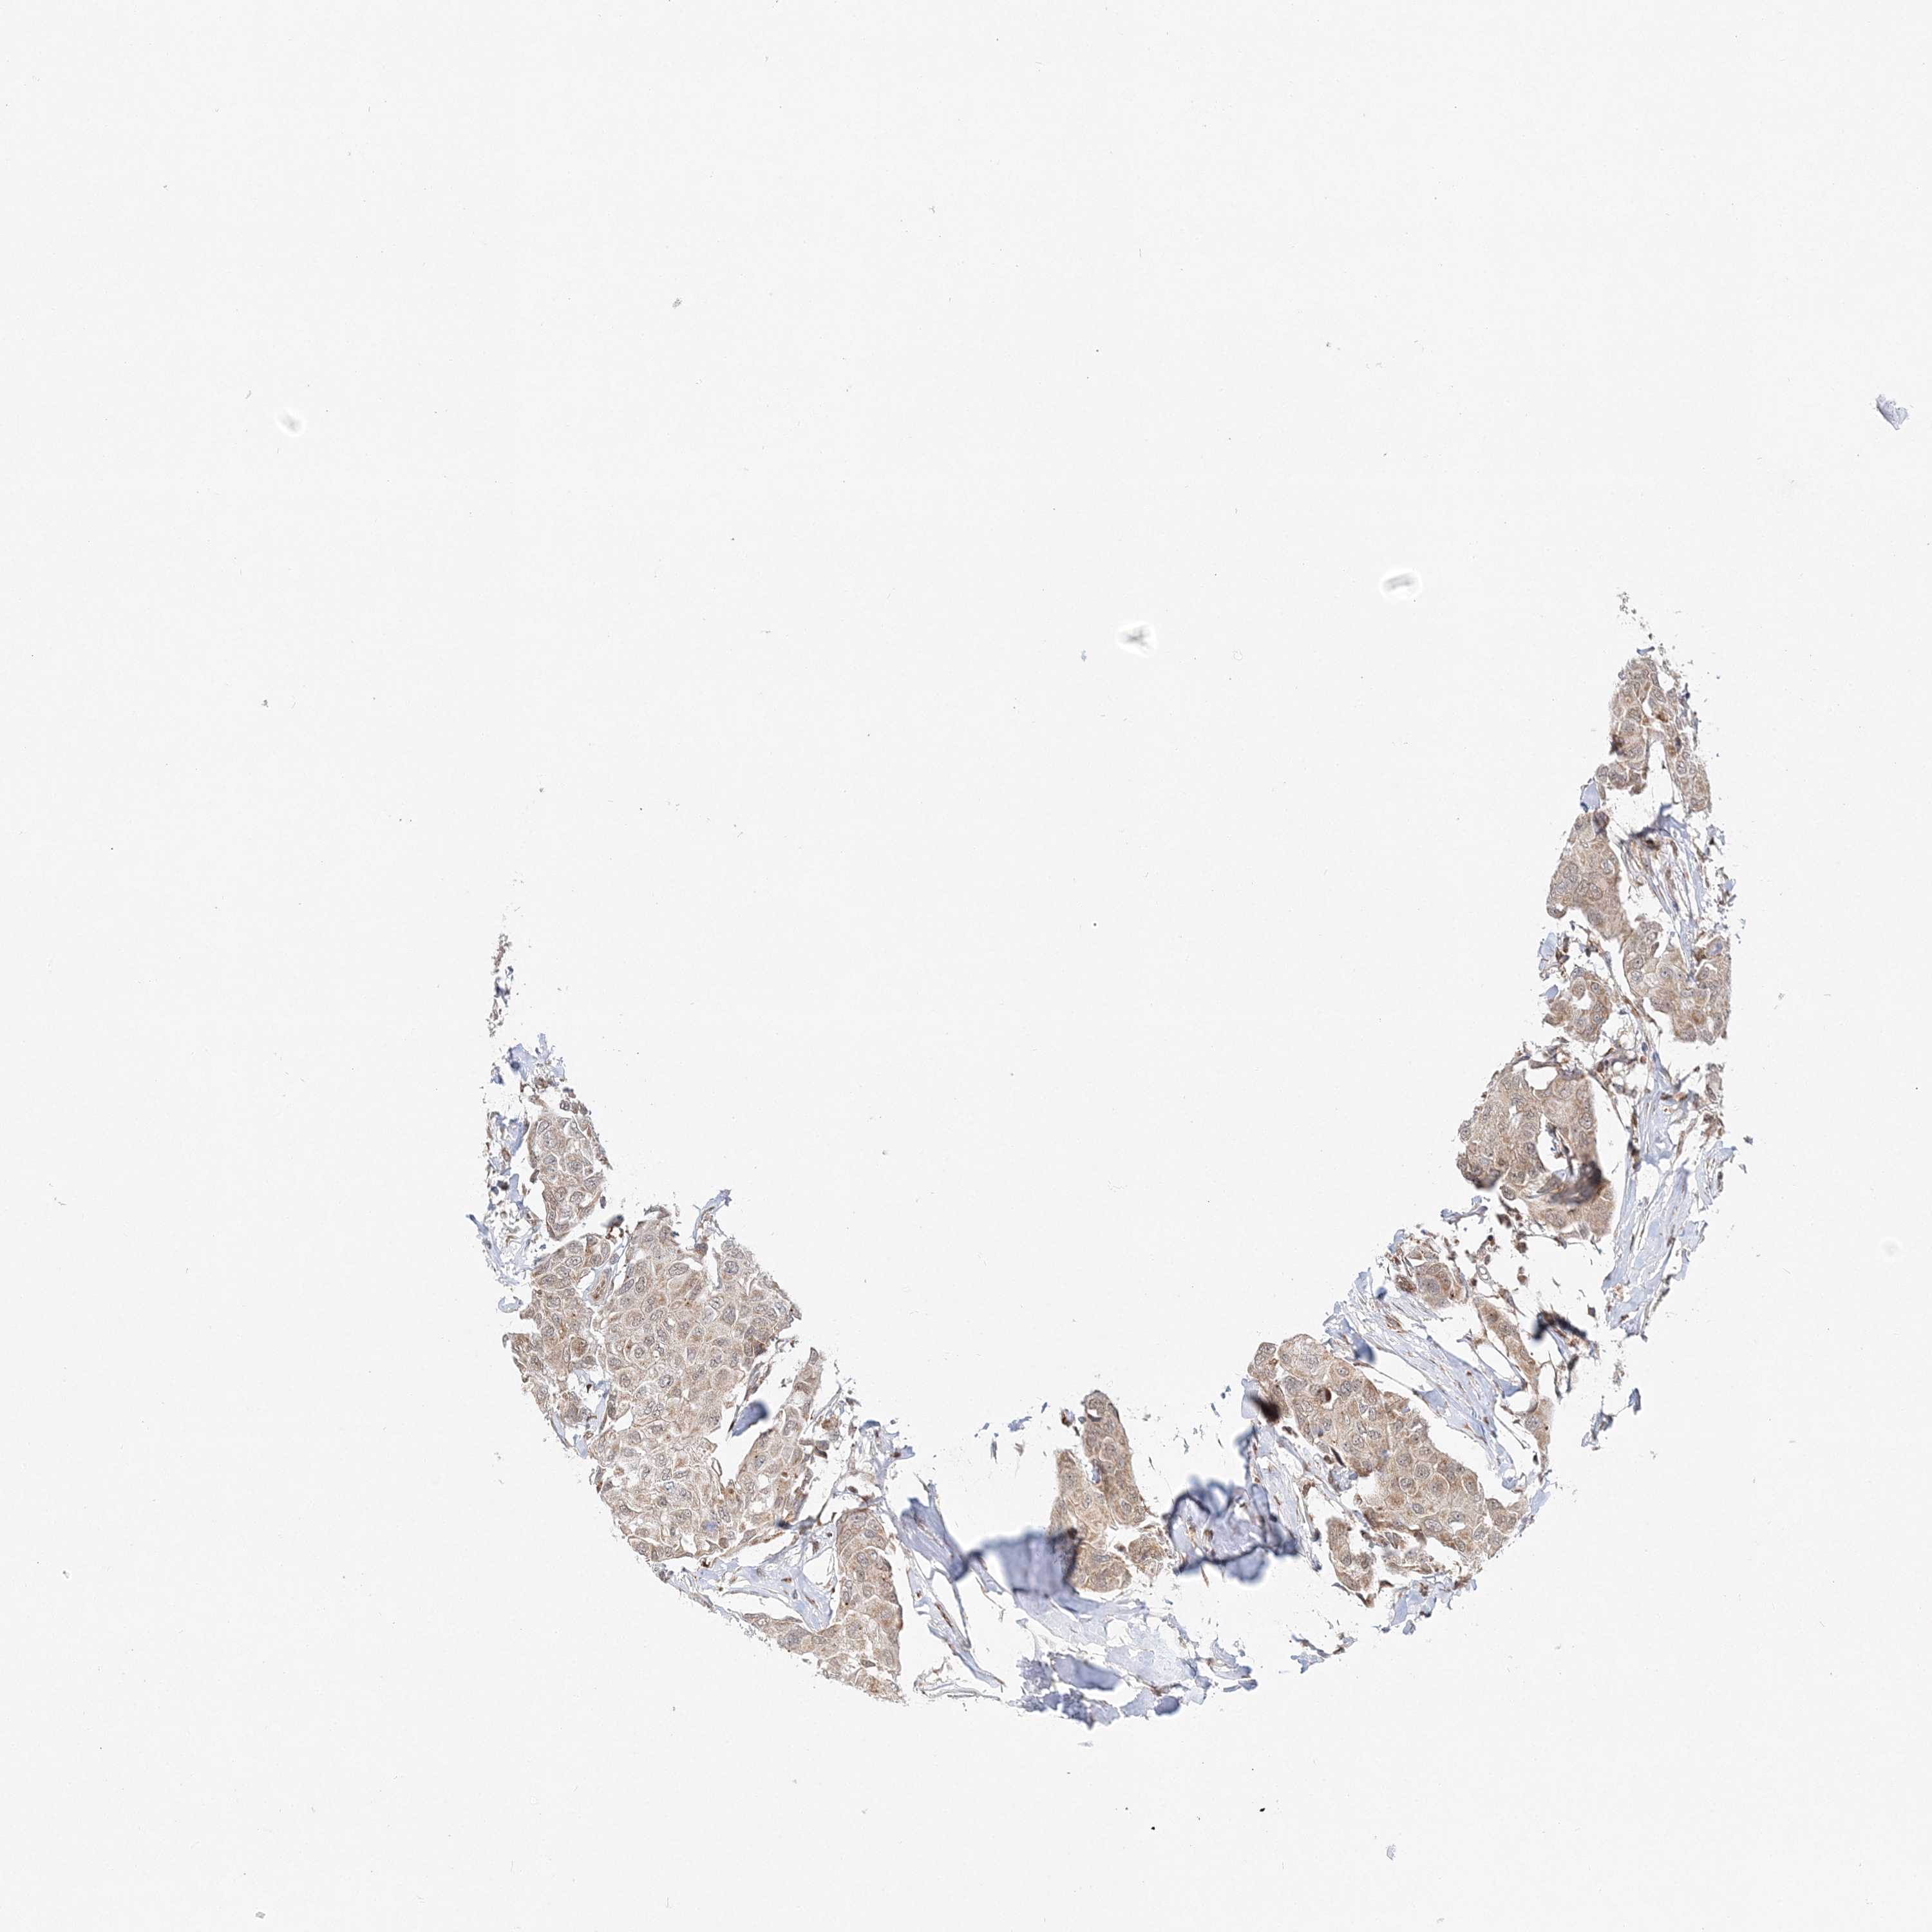

PATHOLOGY BREAST CANCER Show tissue menu

Breast cancer

Human pathology